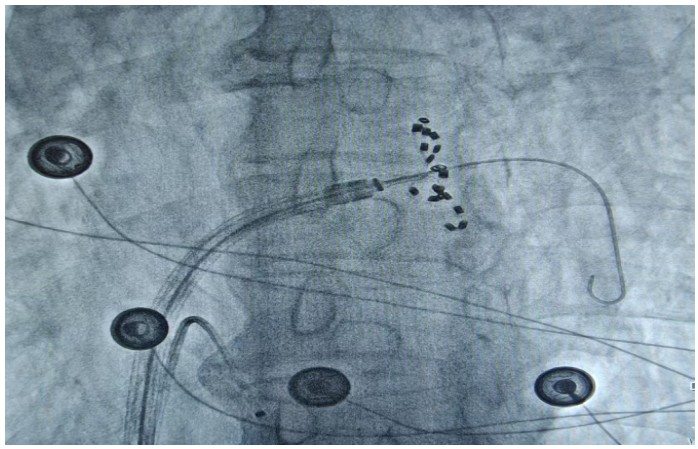

通訊員何紅丹報(bào)道:2025年1月17日,衡陽市中心醫(yī)院心血管內(nèi)科趙慶禧主任醫(yī)師團(tuán)隊(duì)與心血管內(nèi)科電生理團(tuán)隊(duì)協(xié)作,在全麻下成功為一名72歲的男性患者實(shí)施了陣發(fā)性房顫FARAPULSE脈沖電場消融手術(shù)。此次手術(shù)為目前全球最先進(jìn)的PFA消融導(dǎo)管上市后全國首批臨床應(yīng)用,在湘南地區(qū)首次開展,能更精準(zhǔn)地作用于目標(biāo)區(qū)域,減少對周圍組織的損傷,極大程度降低并發(fā)癥的發(fā)生,具有更高的安全性。

趙慶禧介紹,房顫是常見于老年人的心臟問題,通俗的講就是心臟“亂跳”。發(fā)生房顫時(shí)患者心慌心悸難忍,極易誘發(fā)腦卒中等惡性后果,嚴(yán)重危害生命健康。目前,房顫的治療方法包括藥物治療和傳統(tǒng)導(dǎo)管消融。相較于藥物治療和傳統(tǒng)導(dǎo)管消融,脈沖電場消融可選擇性的損傷心肌,而保留血管、神經(jīng)及心臟周圍組織。更快的消融脈沖電場消融(PFA)技術(shù)是最新的消融技術(shù),它能通過高壓電脈沖,實(shí)現(xiàn)消融點(diǎn)細(xì)胞凋亡的目的,達(dá)到抑制紊亂心律發(fā)生的作用。與傳統(tǒng)消融技術(shù)相比,脈沖電場消融具有更高的組織選擇性、更快的消融速度以及更低的貼靠要求,成為臨床迫切需要的突破性創(chuàng)新治療方法,為患者帶來了新的選擇和新的希望。